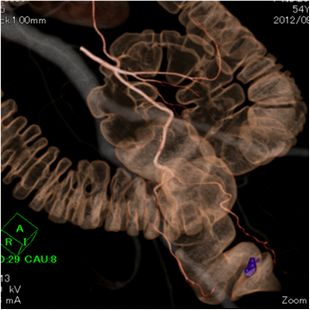

高精度画像診断技術

当院では、各種画像診断装置を導入し、主に各種悪性腫瘍を対象に画像診断、内視鏡的治療、画像介入性低侵襲治療(血管内治療など)、外科的治療に幅広く取り組んでいます。

目的に合った低侵襲な画像診断検査を行い、がんの早期発見および治療に努めています。